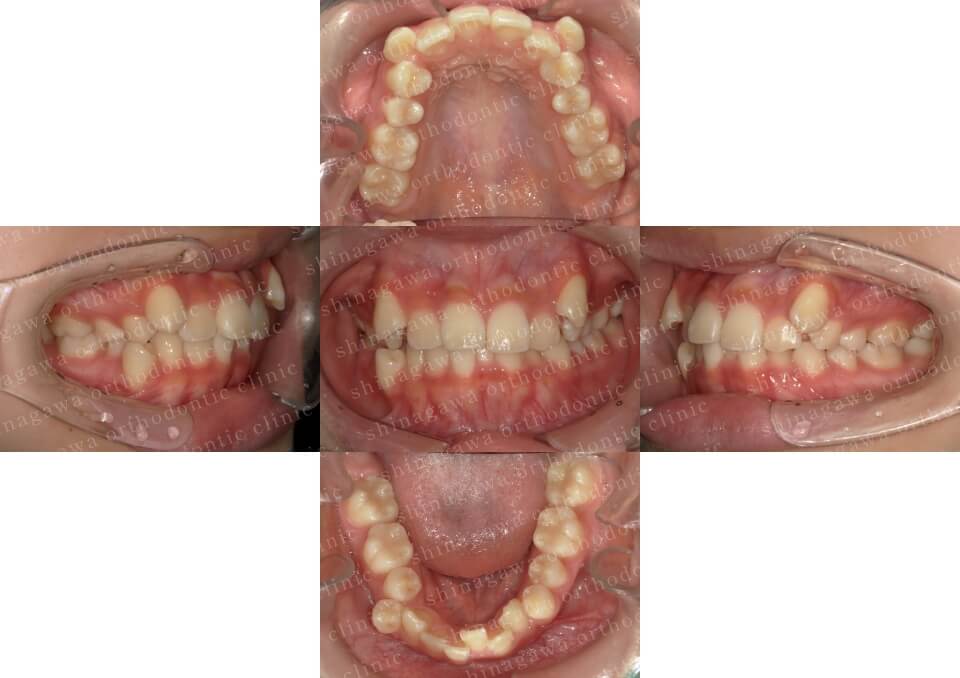

症例8

上顎前突、叢生

| 年齢 | 28 歳 |

|---|---|

| 性別 | 女性 |

| 住所 | 東京都大田区 |

| 主訴 | 出っ歯 |

| 不正咬合の種類(診断) | 上顎前突, 叢生 |

| 装置 | 表ワイヤー |

| 抜歯/非抜歯 | UR4, UL4 |

| 期間 | 20M |

| 費用 | 935,000 円 |

| リスク・副作用 | 矯正治療による歯の移動に伴う痛み, 虫歯, 歯肉退縮, 歯根吸収 |